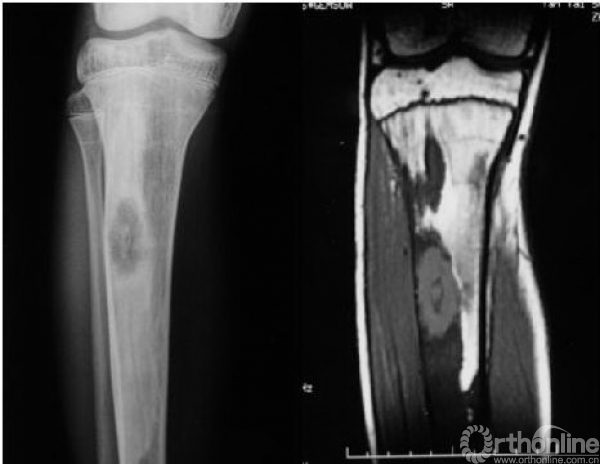

本病女性多见,男女发病率约为1.2:3,多在10岁左右发病,主要症状为轻微疼痛,局部肿胀及压痛。因症状轻微往往被忽略,多数病例是在以后查体或发生病理骨折时才被发现,骨折时疼痛可突然加重,肢体功能障碍,但骨折很少移位(图1),由于受累骨的坚固性受到明显影响,肢体可出现弯曲畸形,发生于股骨近端的常形成髋内翻,被称为“牧羊拐畸形”(图2)。

图1 股骨病理性骨折,没有明显的移位

1、“磨砂玻璃状”改变:这是骨纤维异样增殖症最为常见的特征性X线表现(图5)

图5 左股骨呈“磨砂玻璃状”改变,看不到骨小梁,周围有硬化缘

2、囊状改变:在骨纤维异样增殖症中也比较常见(图6),其病理基础为肿瘤内有液化或出血,尤以股骨颈多见,表现为在磨砂玻璃的基础上出现单囊或多囊性膨胀透亮区。

图6 胫骨有明显的囊性变

MRI表现比较复杂,根据病灶内所含组织的比例不同,表现也不同,多数表现为T1WI和T2WI呈不均匀的低信号,T2WI压脂像上呈中等信号(图8),病灶内有出血或积液时信号明显增高,MRI非常敏感,可早期诊断,并能清楚的确定肿瘤的范围,但对骨皮质的显示不清楚(图9)。

图8 MRI示T1和T2主要为低信号